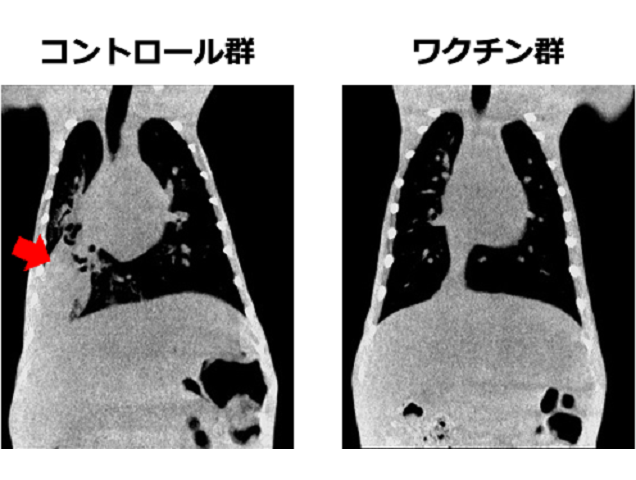

霊長類での有効性を確認! 新規肺炎球菌ワクチンを開発